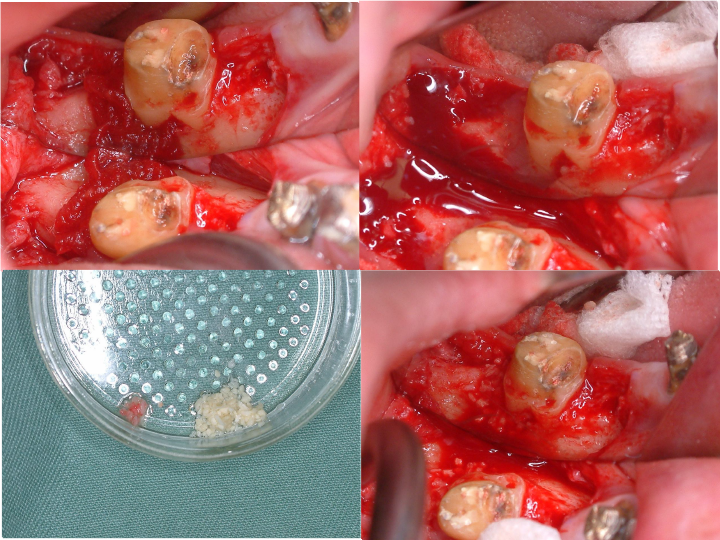

CT所見

ほぼ骨内には埋入できましたが、骨の厚みが足りないため、人工骨を移植し縫合しました。

インプラントの周囲に固い歯茎(角化歯肉)があるとしっかりと歯ブラシがあてることができます。

インプラントの周囲に固い歯茎を作るために歯茎(角化歯肉)の移植を行いました。